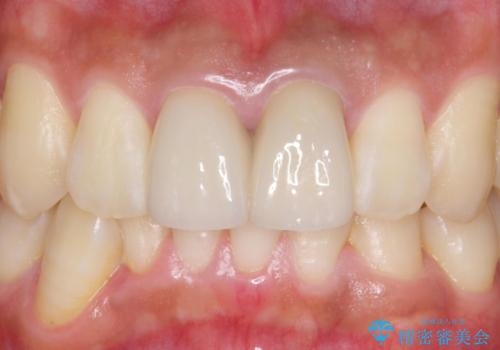

歯のガタつきも解消することができました。

e-maxクラウンでは仮着ができませんが、今回は一回でご満足いただける修復ができました。